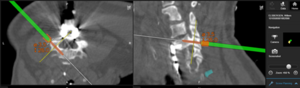

Seit 2017 führen wir unsere Stabilisierungs- und Versteifungsoperationen mit einem intraoperativen CT (s.o. AIRO©, Fa. Brainlab) durch. Diese intraoperative Computertomographie liefert direkt im Operationssaal während des Eingriffs hochauflösende Bilder von der Wirbelsäule. Zusammen mit einer Navigationssoftware wird ein dreidimensionaler Plan der entsprechenden Körperregion erzeugt. Mit Hilfe der Bildgebung können wir die notwendigen OP-Schritte plangerecht umsetzen und z.B. Implantate mit sehr hoher Präzision einsetzen. Gerade bei komplizierten Eingriffen an der Wirbelsäule hilft die neue OP-Technik, Patienten sicher und schonend zu therapieren. Die intraoperative Bildgebung, direkt im OP, erlaubt komplexe Operationen genauer und sicherer durchzuführen und dem Operateur noch während der Operation das Ergebnis zu überprüfen und bei Bedarf zu optimieren. Belastende Folgeoperationen sind so deutlich seltener und die Behandlungsqualität und Sicherheit für Patienten dadurch erheblich verbessert.